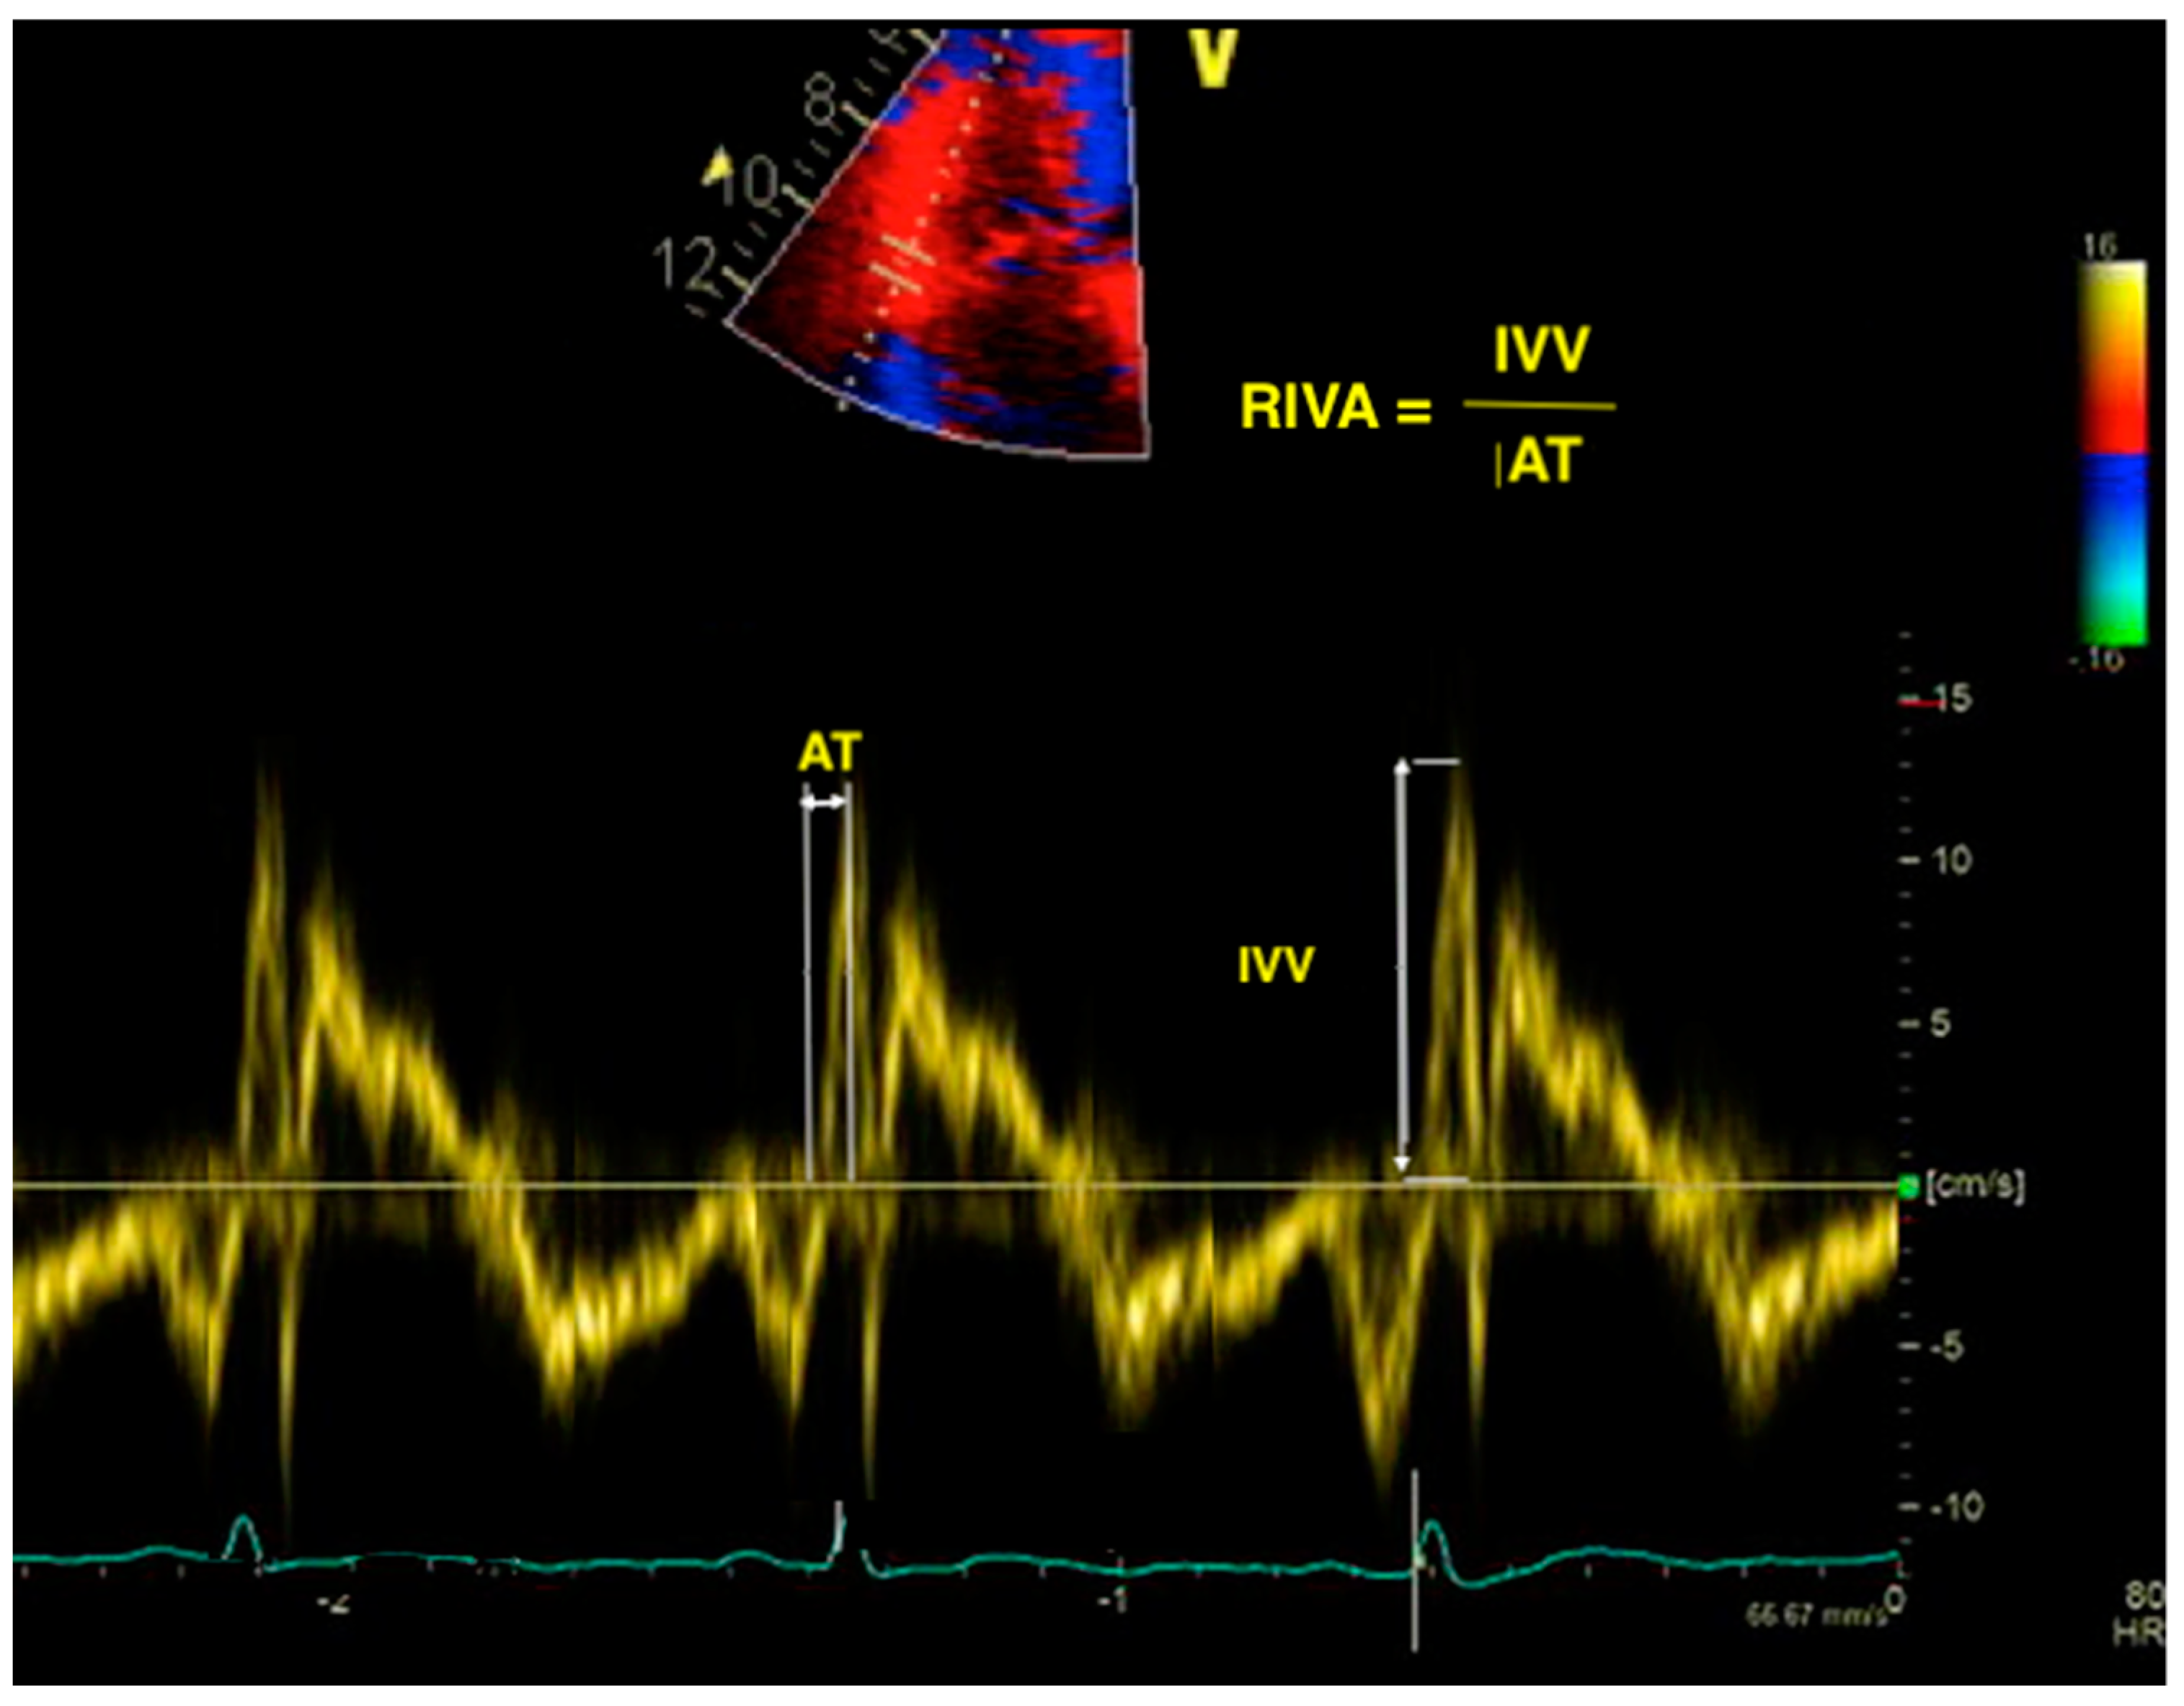

Myocardial acceleration during isovolumic contraction is usually obtained using TDI at the lateral tricuspid annulus in the apical four-chamber view. It is calculated as the peak myocardial velocity during isovolumic contraction divided by the time needed to reach this velocity (Figure 2). While it has the advantage of being relatively load-independent [30], it has a large confidence interval around the normal values [29]; hence, it is not recommended for routine use and no reference value for this parameter has been proposed by the latest guidelines [26]. Consequently, its prognostic utility has not been broadly studied. However, Sciatti et al. found RV isovolumic acceleration to be a better predictor for cardiac death and rehospitalization in patients with HF and reduced LVEF than traditional parameters of RV systolic function such as TAPSE, RV FAC, and S’ wave [55].

Figure 2.

Calculation of RIVA using TDI. RIVA—right isovolumic acceleration; TDI—tissue Doppler imaging; IVV—isovolumic velocity; AT—acceleration time.